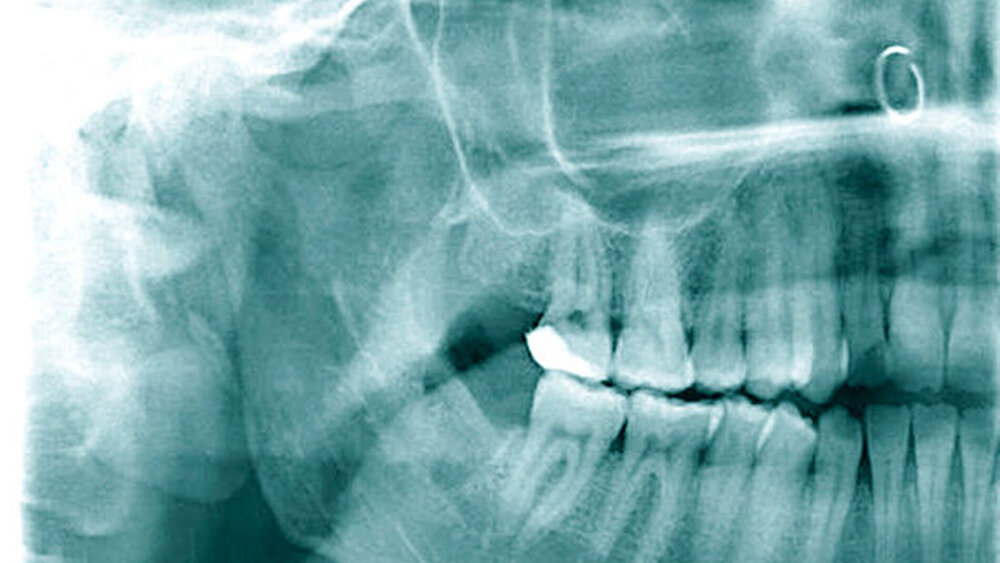

Abbildung 1 dokumentiert den Röntgenbefund des ersten und des vierten Quadranten. Bei Verdacht auf eine Neurotmesis des rechten N. lingualis (lingual nerve; LN) und eine Axonotmesis des rechten N. alveolaris inferior (inferior alveolar nerve; IAN) während der Weisheitszahnentfernung wurde nach Erörterung der Therapiemöglichkeiten mit der Patientin die Indikation zur zeitnahen operativen Nervendarstellung und -rekonstruktion gestellt.

Postoperativ berichtete die Patientin über eine Verbesserung der Sensibilität im Bereich des Unterkiefers rechts sowie über ein gelegentliches Kribbelgefühl im Bereich der Zunge rechts. Zur Verbesserung der körperlichen Nervenregeneration wurde Vitamin B12 oral substituiert. Abbildung 5 dokumentiert die postoperative Röntgenkontrolle.